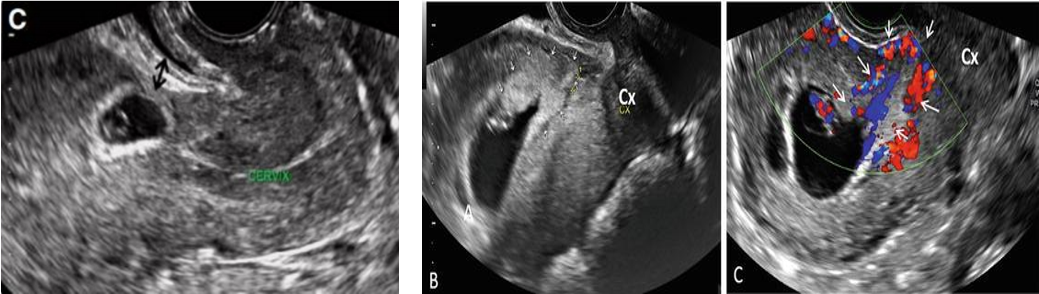

Trên lâm sàng chẩn đoán TNTCSMLT sớm rất khó. Chẩn đoán căn cứ trên tiền sử, bệnh cảnh lâm sàng như đau bụng, rong huyết và quan trọng nhất là siêu âm Doppler màu, một số trường hợp khó cần xác định bằng MRI và nội soi buồng tử cung cũng được dùng trong chẩn đoán.

Siêu âm đầu dò âm đạo có độ nhạy 85%. Siêu âm đầu dò âm đạo giúp quan sát rõ túi thai và tương quan với sẹo MLT. Kết hợp siêu âm qua thành bụng tạo ra hình ảnh rộng của tử cung và phần phụ và đo được khoảng cách giữa túi thai và bàng quang. Qua đó cũng đó được độ dày vách cơ tử cung giữa bàng quang và túi thai.

Tiêu chuẩn chẩn đoán TNTCSMLT trên siêu âm đầu dò âm đạo theo RCOG

• Buồng tử cung trống không có túi thai trong khoang nội mạc tử cung

• Túi thai hoặc khối tế bào nuôi bám vào vùng vết mổ cũ trước ở đoạn eo tử cung

• Lớp cơ tử cung giữa bàng bang và túi thai biến mất hoặc rất mỏng

• Tăng sinh mạch quanh khối qua siêu âm Doppler

• Kênh cổ tử cung trống.

Hình ảnh siêu âm đầu dó âm đạo thai ngoài tử cung ở vết mổ cũ